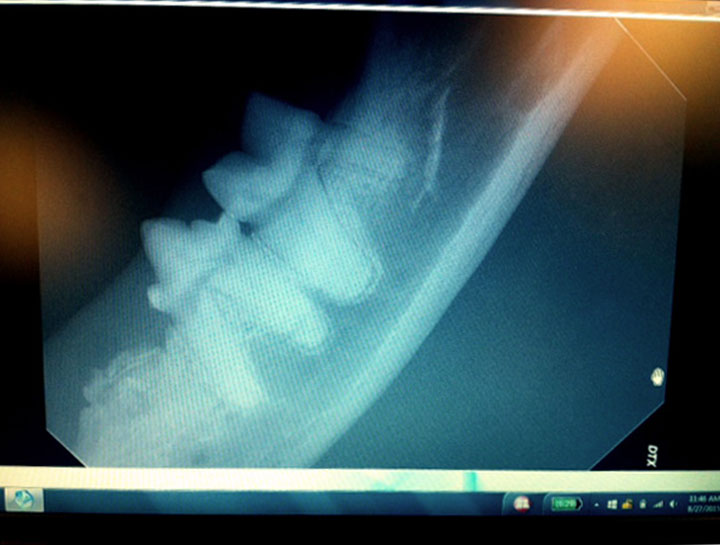

Digital Dental Radiology

Insight into underlying issues.